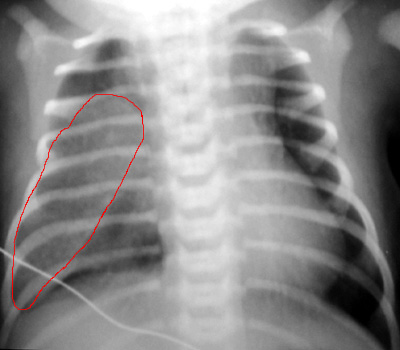

This is Congenital Lobar Emphysema.

This is a more difficult case because it does not look like typical, hyperlucent CLE.

Remember that CLE is more opaque in the initial period due to the retention of fetal pulmonary fluid.